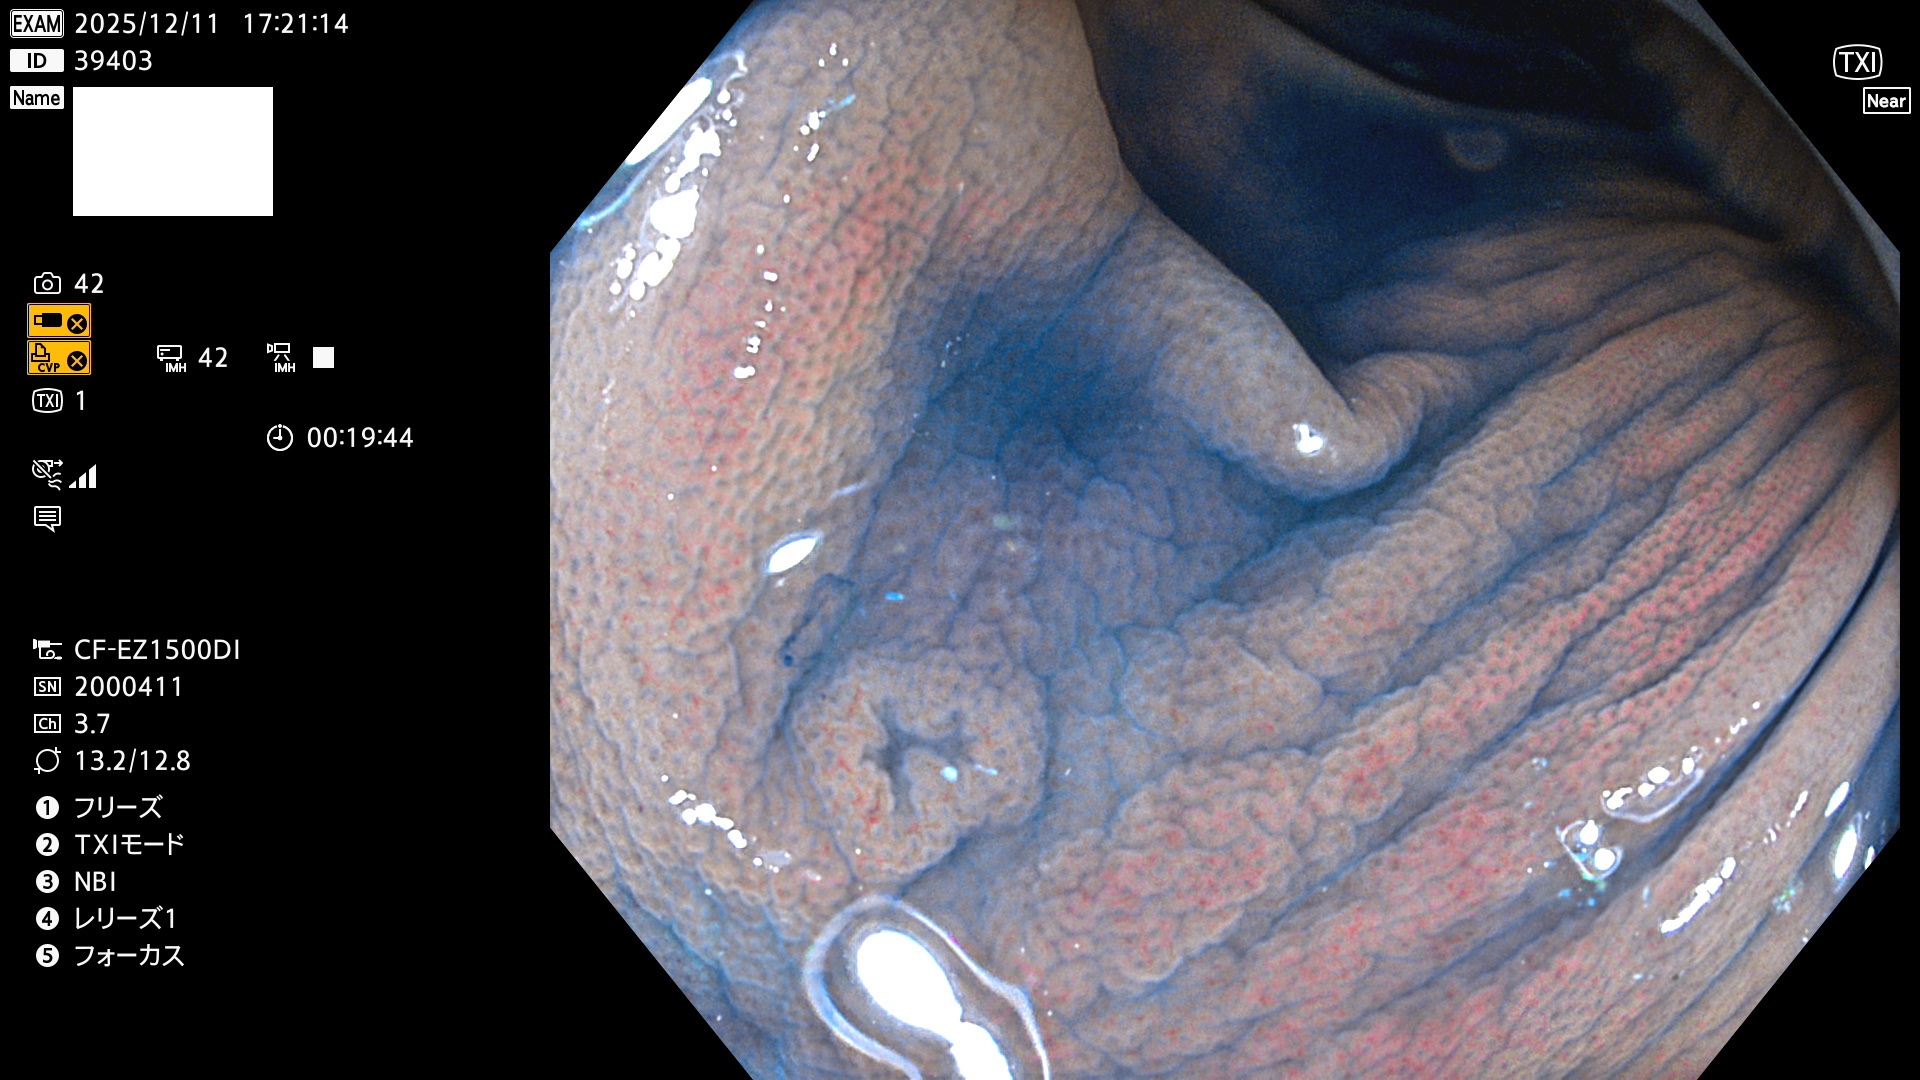

完全に平坦な物をUb、陥凹している物をUcと呼びます。Ubは認識が困難で、Ucはびらん(炎症)と紛らわしいために見落とされやすく、「内視鏡後・大腸癌」の原因になります。

専門的)Uc=De Novo癌? 内視鏡の解像度が低かった時代、このような説もありました。しかし今日の高精度内視鏡では良性の微小なUc型腺腫(APC遺伝子異常の腺腫)が日常的に見つかります。Ucこそが多段階発癌(Adenoma-Carcinoma Sequence)のMain Routeです。

専門的)細胞生物学的Ucの再定義UcをPitと形態学で定義するのは医学的には全く不毛です。Ucの本質はIntraTumor HeterogenityとTumor Dormancyが微小病変に見られる点です。これは早い腫瘍進化=ゲノム不安定性を意味します。そのような病変は隆起型でも形態によらずUcと定義すべきです。なぜなら1年後には陥凹し典型的Uc(最悪の場合NPG癌)になるからです。

毎週の検査(木・金・土・日)に発見されたUbとUc型・腺腫を、その週の日曜の夜にUPし1週間、提示します。

2025年11月27日〜12月7日の7日間(70件)で6個 (Uc_ADR=6個/70人=9%)